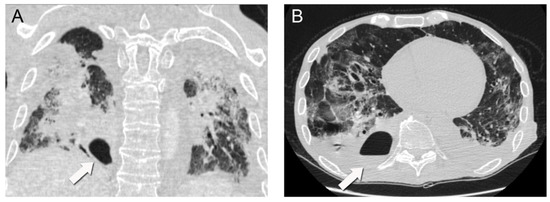

A repeat chest CT scan demonstrated multiple converging consolidated lesions in both lungs with scattered areas of ground glass. Most notably, in the posterior basal segment of his right lower lung lobe, an intraparenchymal thin-walled cavity measuring 7 × 4 cm2 in diameter was observed. The presence of an air-fluid level was indicative of a pulmonary abscess associated with the previous areas of dense consolidation (Figure 2). It was hypothesized that the pulmonary abscess was possibly associated with a bacterial superinfection caused by the COVID-19 disease. Due to unstable respiratory conditions, bronchoscopy was not performed. However, direct cultures were obtained via thoracentesis under ultrasound guidance and fluid aspiration. Both blood and aspirated fluid cultures failed to identify a causative microorganism.

Figure 2.

Subsequent chest CT scan demonstrating a 7 × 4 cm2 intraparenchymal abscess (arrows) with an air-fluid level in the posterior basal segment of the right lower lung lobe (coronal (A), axial (B)).

The development of cavitating lesions with an air-fluid level following viral pneumonia have been previously described [7]. They are the result of a necrotizing process in areas with initial consolidation and superinfection [7].

The patient’s initial chest CT demonstrated significant areas of diffuse consolidation and patchy ground glass opacification. These are findings which have previously been associated and described with COVID-19 viral pneumonia [7]. In addition, in hindsight there seemed to be a focus of atelectasis and consolidation in the right lower lobe which could represent the precursor of the lung abscess.